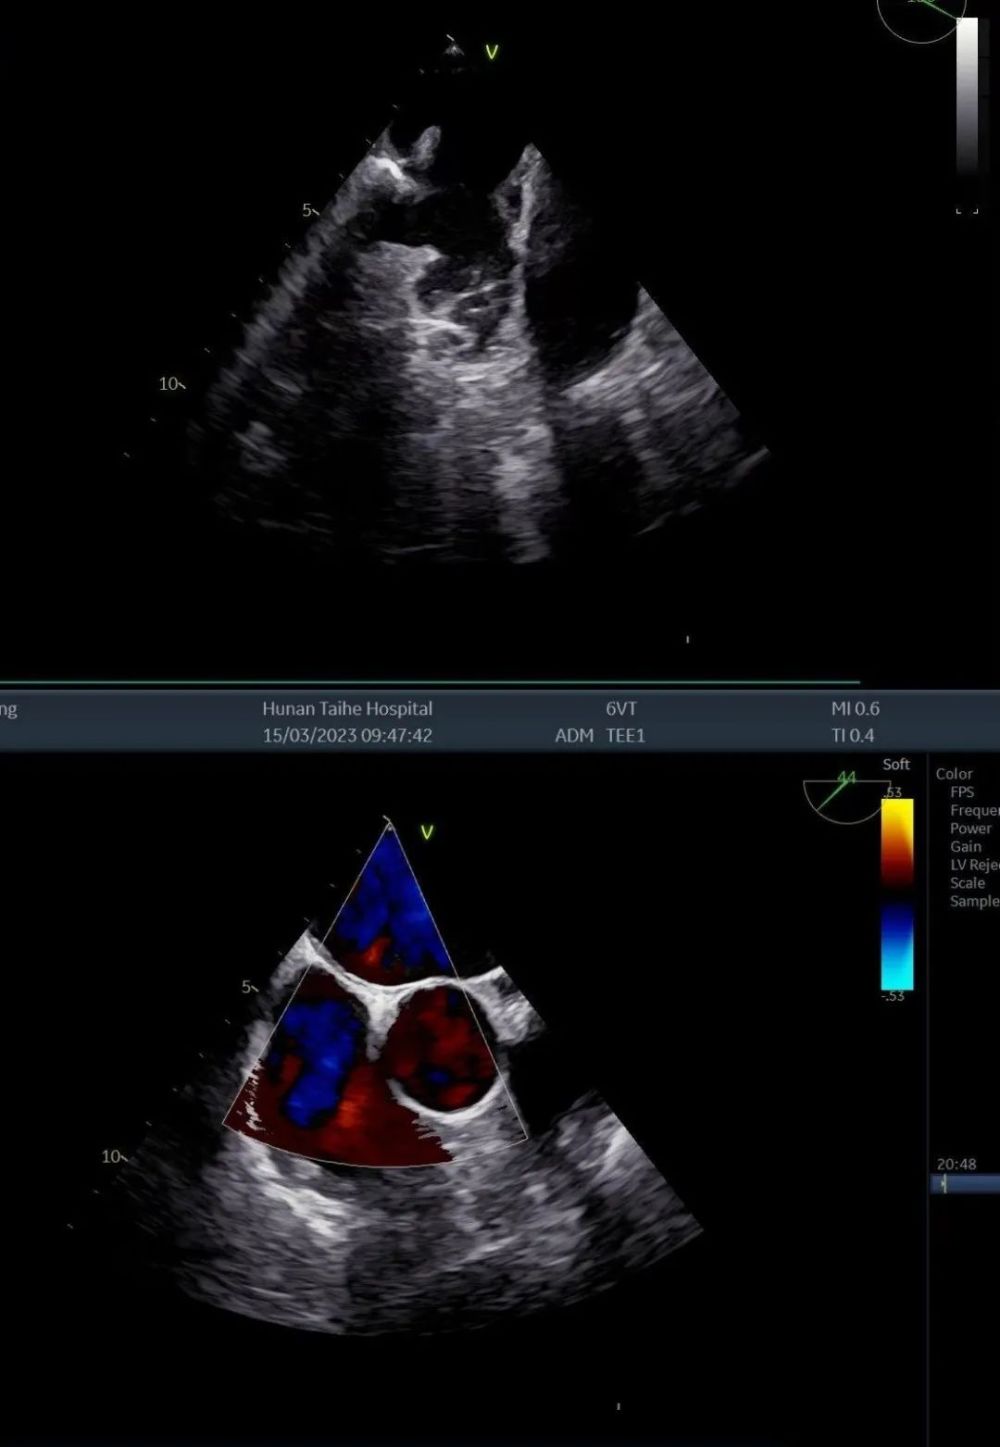

为患者实施了经食管超声心动图检查,结果显示:患者房间隔连续完整,左